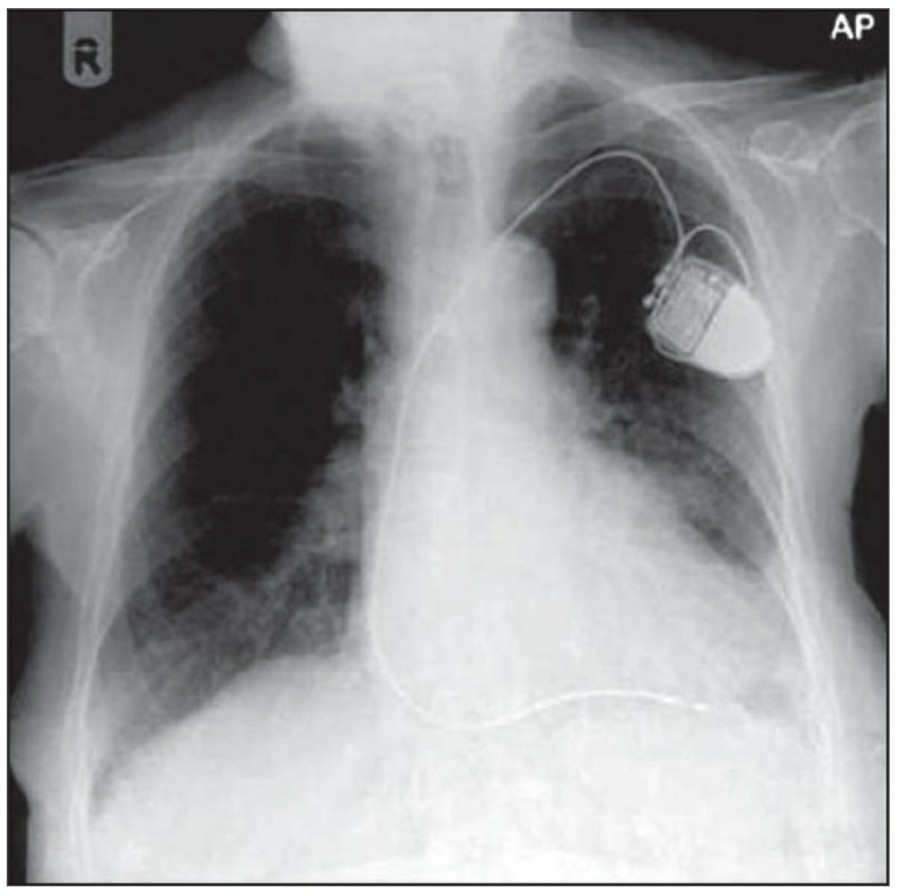

Cardiac pacing devices

Temporary cardiac pacemaker는 cephalic vein이나 subclavian vien을 통해 right ventricl에 거치시킨다. AP, lateral chest X ray가 위치 확인을 위해 필요한다. Cardiac pacemaker의 tip은 심첨부에 위치해야 하며, pacemaker wire의 line이 꺾여 있어서는 안 된다. Lateral radiograph가 cardiac trabeculae 안에 묻혀 있는 tip을 확인하는데 도움이 된다. 제대로 거치된 게 맞다면 그 tip은 epicardial fat pad의 3, 4mm 안에 있어야 하며, 그 이상 넘어간다면 myocardium 천공 가능성이 있다. Coronary sinus 안에 들어갔을 경우 lateral radiograph 상에서 posterior 쪽에서 발견할 수 있다.